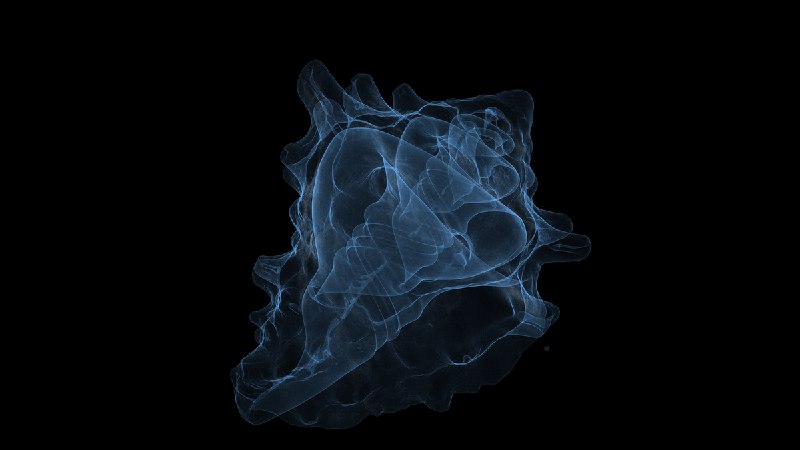

#React #3D 使用 React Three Fiber 制作效果:在云端渲染 CT 扫描动画

https://barndoors.lumafield.com/rendering-ct-scan-animations-in-the-cloud/